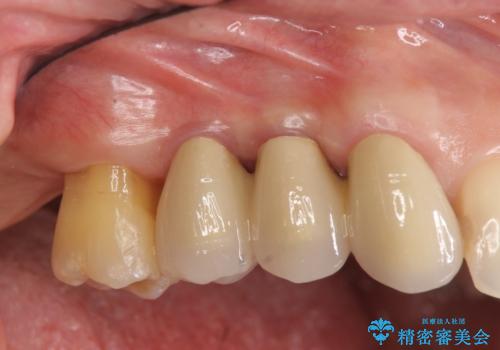

[歯周病治療] 再生療法で歯を残す②

担当医 大元洋佑

![[歯周病治療]  再生療法で歯を残す②の症例 治療後](https://seimitsushinbi.jp/wp/wp-content/uploads/2019/01/041488131c79b655b9a827603884c4ed-500x350.jpg)